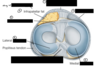

stability of knee joint: * bony factors * ligamentous factors * muscular factors

* bony factors: articular surfaces **do NOT fit nicely**: **massive femoral** condyles vs **small and shallow tibial** condyles, **shallow** articular surfaces of **femur and patella** * ligaments: medial and lateral **collateral** ligaments, **cruciate** ligaments * muscles: surrounding muscles and tendons ## Footnote articular surfaces: 1. femorotibial articulations: femoral **condyles** with tibia **condyles**, with **menisci** in between 2. femoropatellar articulations: **patellar surface** of femur with patella

211

function of cruciate ligaments

* anterior cruciate ligament (ACL): prevents **POSTERIOR displacement of femur** on tibia (= anterior movement of tibia relative to femur) and **hyperextension** of knee joint * posterior cruciate ligament (PCL): prevents **ANTERIOR displacement of femur** on tibia (= posterior movement of tibia relative to femur) and **hyperflexion** of knee joint ## Footnote think of their origins and insertions: * ACL originates at **ANTERIOR intercondylar** area of **tibia** → inserts at **POSTERIOR** part of **LATERAL femoral condyle** * PCL originates at **POSTERIOR intercondylar** area of **tibia** → inserts at **ANTERIOR** part of **medial femoral condyle** to understand extension/flexion, think of it this way! e.g. **extension** → **femur pushes tibia forward** slightly (= anterior movement of tibia relative to femur) ⇒ pulls on ACL

212

why does medial meniscus get torn more often

1. **medial** meniscus is firmly **fixed to tibial collateral ligament** → lesser excursion during rotatory movements (i.e. lesser movements when flex/extend knee) ⇒ more likely to be crushed or torn 2. while **lateral** meniscus is **separated from fibular collateral ligament** by **popliteus** muscle AND **popliteus pulls** lateral meniscus **backwards** ⇒ preventing crushing bet articular surfaces 3. **medial** meniscus is **broader at the back** while lateral meniscus is more circular

214

unhappy triad: * when does it occur * what ligaments does it involve

* foot is planted, **knee** is slightly **flexed**, external rotation of tibia, boom **valgus force** (i.e. abduction of knee joint) applied **to lateral knee** * ligaments: 1. **MCL**: bcos of overabduction of knee joint 2. **ACL** 3. **medial meniscus**: bcos firmly attached to MCL